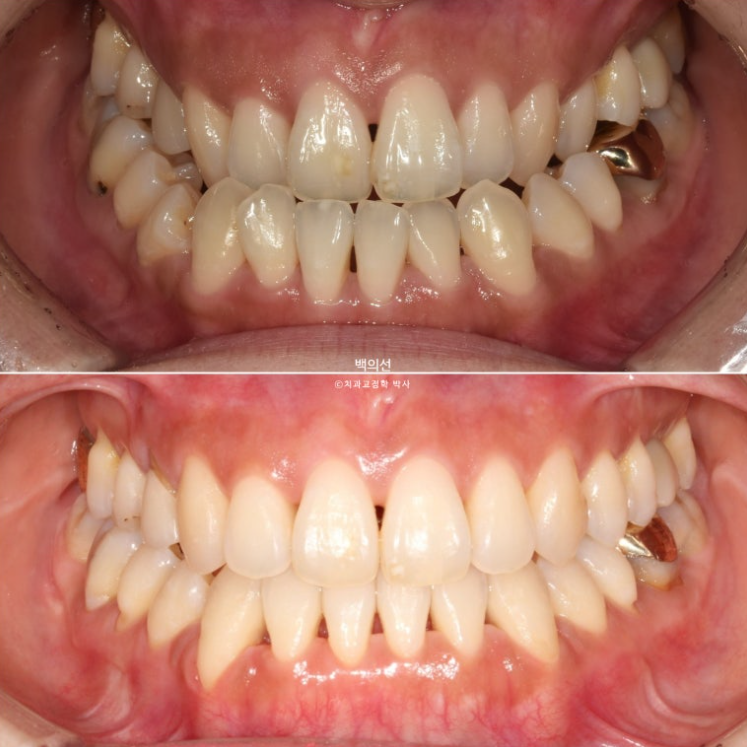

오늘은 주걱턱 즉 골격성 3급 부정교합을 소개해드리려고 합니다

골격성 3급 부정교합의 경우 정도에 따라 양악수술까지 필요한 경우가 있습니다.

24.01~25.07

삐뚤 앞니는 가지런해졌습니다.

이제 전후 비교 보겠습니다. 총 치료기간은 1년 반, 재제작은 1회 했습니다.

앞니 뿐만 아니라 어금니 반대교합도 함께 개선되었습니다.

중심선은 개선되었습니다.